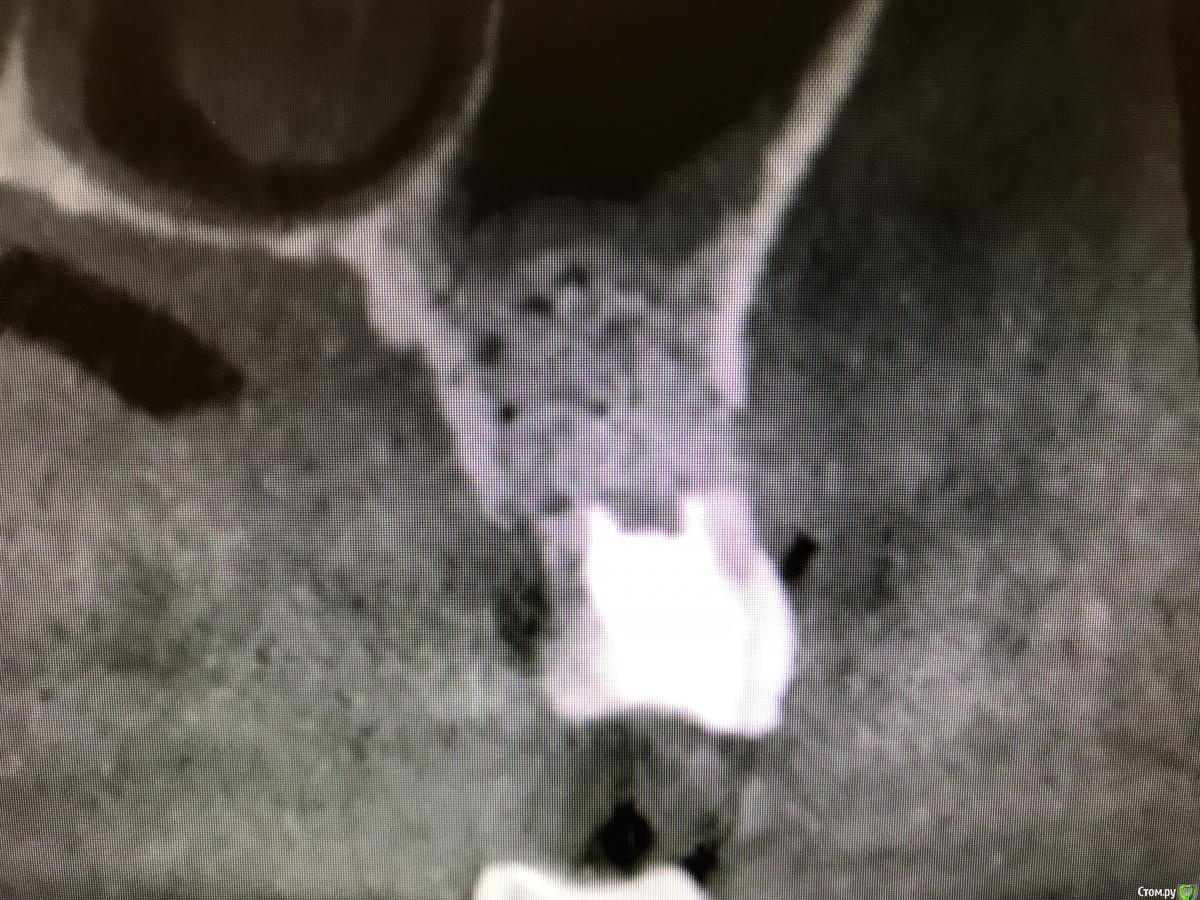

колесников Опубликовано 21 апреля, 2018 Поделиться Опубликовано 21 апреля, 2018 (изменено) Расширяем показания. В первом случае пациент наотрез отказался расставаться с коронковой частью зуба. Проведена консервация ,корень 25 удалён до круговой связки ,коронка установлена в лунку и фиксирована композитной шиной,из прикуса выведена. (25,26 позднее сделаю одномоментно). Итог не очень. Ввиду отсутствия болевых ощущений ( жирный плюс метода) пациент жевал без ограничений,шина откололась на 4ый день и он самостоятельно все разобрал. На момент осмотра лунка регенерирована на 2/3. ( фото нет,был расстроен). Идея мне понравилась,при случае ещё раз воспроизведу,но шинирую поосновательней.Второй случай. Одномоментная имплантация 36. Имплант с небольшим торком,пациент уезжает . Как закрыть лунку,сохранить графт и десневой контур? Для индивидуального формирователя не был заказан временный абатмент. Поверх формирователя высотой 3мм,оставил латку из радикса по форме лунки и фиксировал композитом. (Формирователь докрутил). Вид через 3 дня. Первичными результатами доволен,буду практиковать. Изменено 21 апреля, 2018 пользователем колесников 2 Ссылка на комментарий